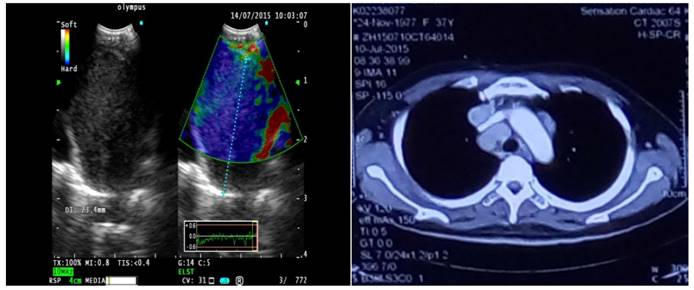

As one result of this study we found false positive LNs in the Type 3 group classified histologically as sarcoidosis [Figure 2], due to fibrous tissue hyperplasia in lymphoid tissue leading to increased hardness. For false negative patients in type 1 lymph nodes, the final pathologic result was adenocarcinoma [Figure 3], because the lymph node invasion by tumor cells caused partial lymphoid tissue liquefaction. Due to the above-mentioned reasons, operators should combine clinical examination with patients medical history in order to avoid misdiagnosis. There are two groups of patients; one is tuberculosis patients, with caseous necrosis and more calcifications which increase organization hardness. The second is chronic lymphadenitis patients: Here the tissue hardens by increased fibrous tissue hyperplasia. In these 2 groups the operator should pay high attention during EBUS elastography examination of superficial lymph nodes.

Figure 3

A case of 11L with Type 1 lymph node on EBUS elastography, pathological results show poorly differentiated adenocarcinoma.